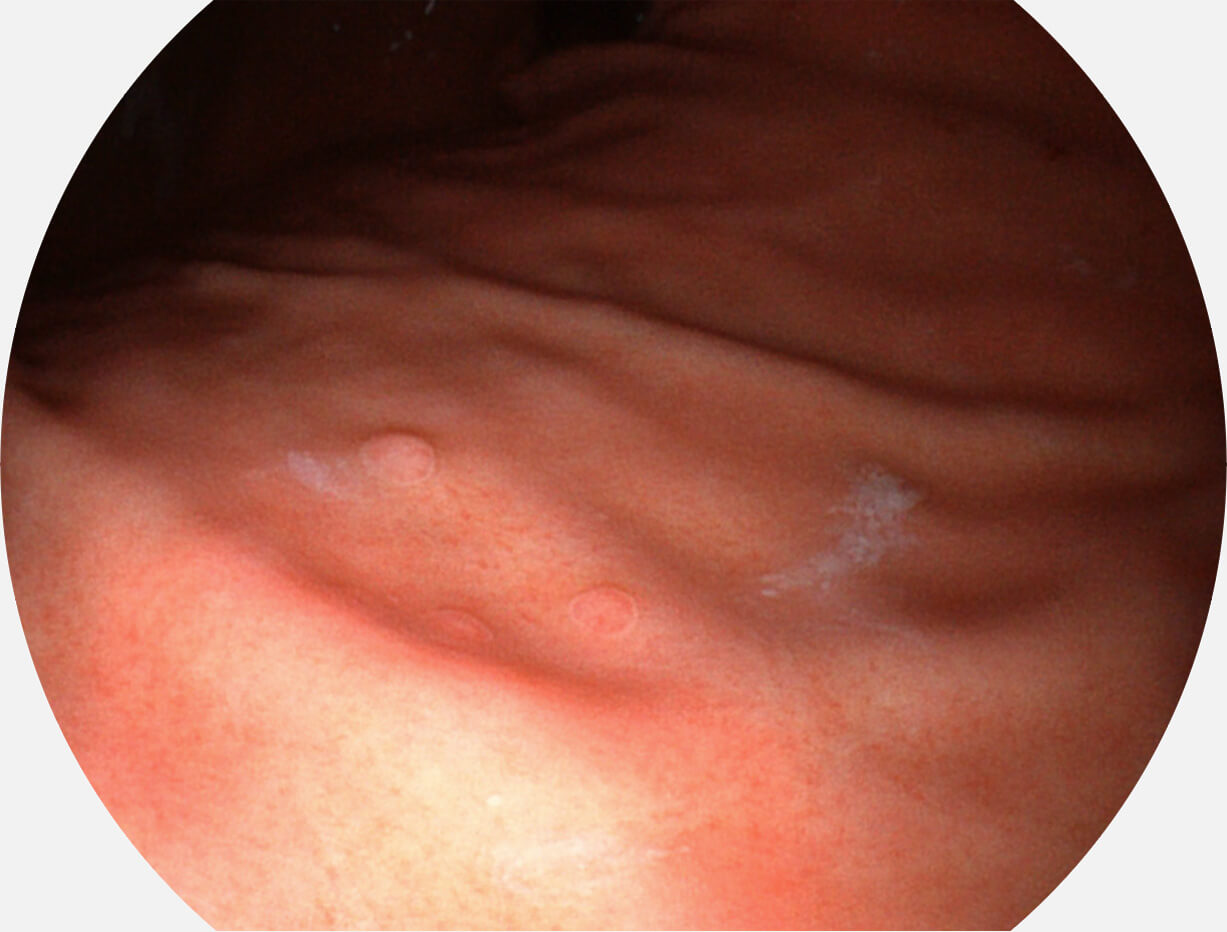

光电复合染色成像技术

Versatile Intelligent Staining Technology, VIST

强调浅层黏膜结构的同时,保证照明亮度和提升浅层微血管与中层血管颜色对比度,病变边界更清晰。

• 白光图像 VIST图像